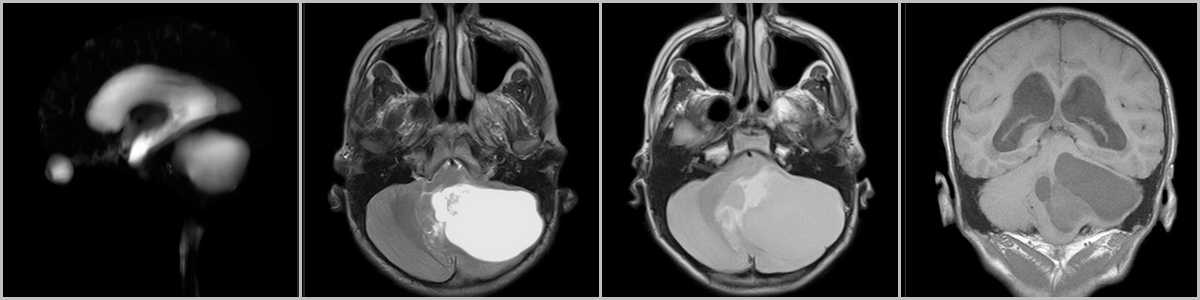

Рис.7

При росте опухоли определяется увеличение кисты (рис.7), а так же оказываемый ею “масс-эффект” со сдавлением IV желудочка и формированием окклюзионной гидроцефалии с расширением III и боковых желудочков, а так же сглаживанием борозд.

Рис.8